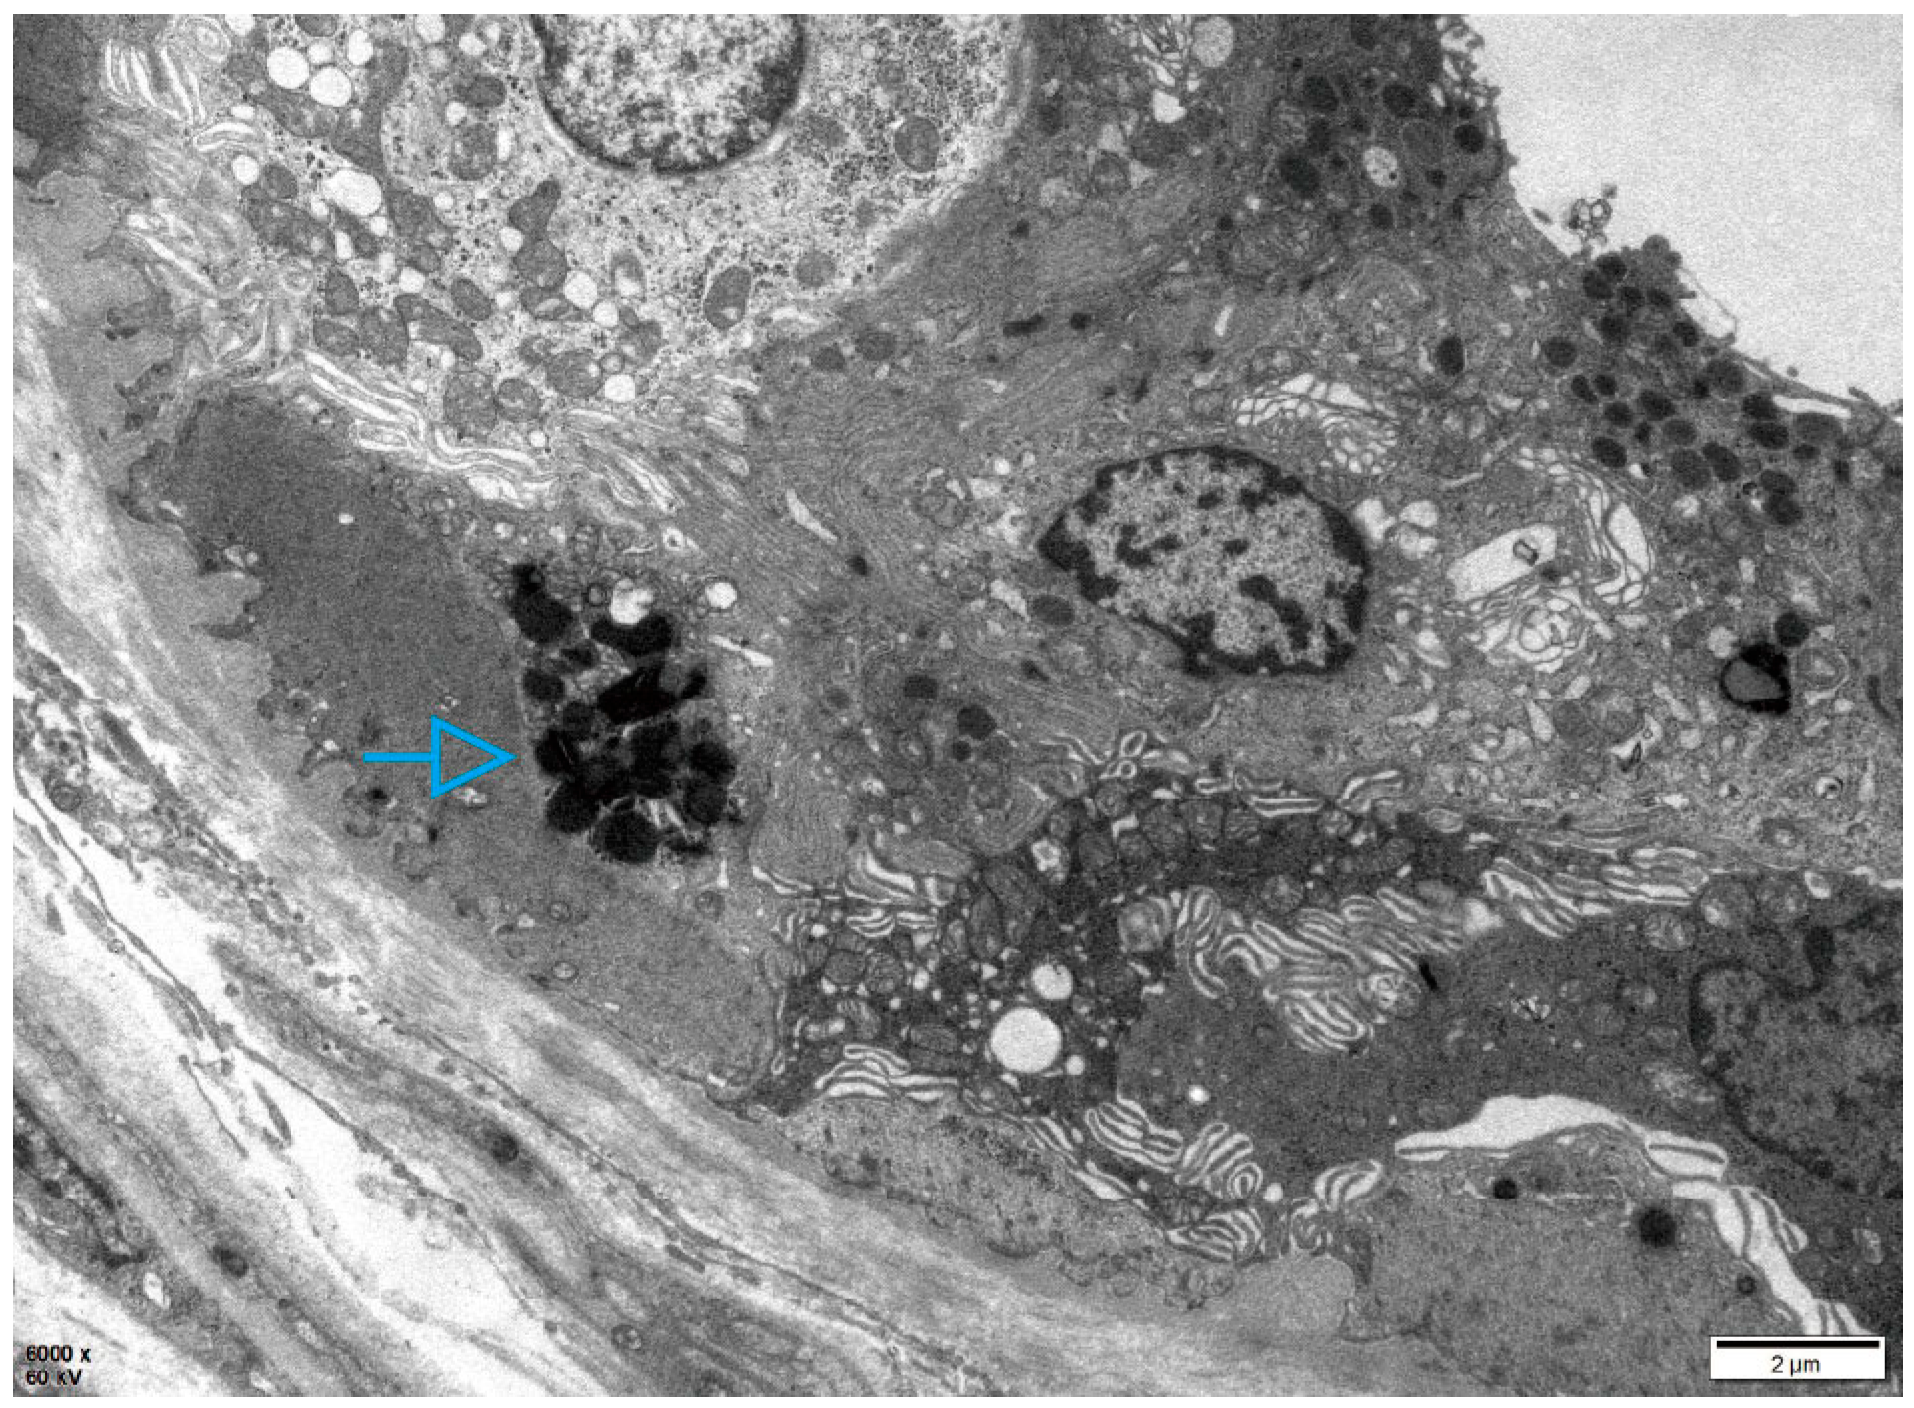

2. Case Description

2.1. Patient 1

2.2. Patient 2